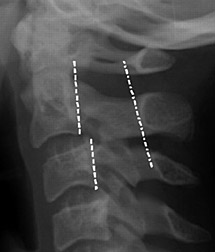

C3 vertebral body - Copyright – Stock Photo / Register Mark Figure 3: Anterior wedging of the C3 vertebral body; a normal finding in the pediatric spine. Absence of Lordosis: The absence of lordosis, although potentially pathologic in an adult, can be seen in children up to 16 years of age when the neck is in a neutral position. The normal posterior intraspinous distance is a good indicator of ligamentous integrity and should not be more than 1.5 times greater than the intraspinous distance one level either above or below the level in question. In children, the flexion maneuver can increase the distance between the tips of the C1 and C2 spinous processes. This widened C1-2 intervertebral distance is a normal finding and should not be misinterpreted as ligamentous injury. This finding is postulated to be secondary to the tight ligamentous attachment between the skull base and C1.

Prominence of Prevertebral Soft Tissues: Whereas prominence of the prevertebral soft tissues in adults indicates edema or hemorrhage on the lateral cervical view, this finding can be normal in children. A prevertebral space of less than 6 mm at the level of C3 is considered normal in children and is dependent on the phase of respiration. (Figure 4)